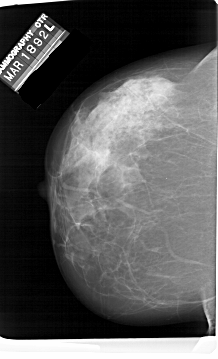

A_1414_1.LEFT_MLO

LEFT_MLO LINES 6646 PIXELS_PER_LINE 4441 BITS_PER_PIXEL 12 RESOLUTION 43.5 NON_OVERLAY